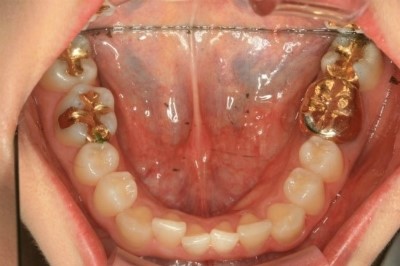

다음은 구강 촬영 사진입니다, X레이보다 확연하게

아랫니의 틀어짐이 보이실 겁니다.